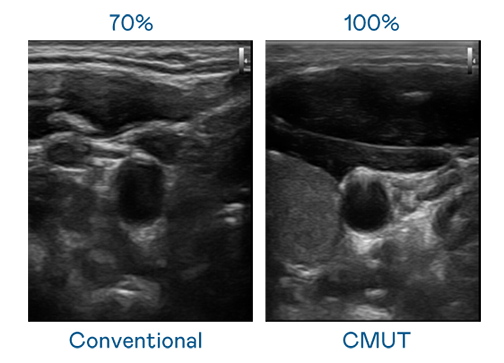

CMUT 技術是一種用電容式微機電元件來產生超音波訊號的技術。與傳統 PZT 壓電式技術相比,CMUT 頻寬增加 30%,更寬頻的超音波訊號讓影像解析度大幅提升,是實現高影像品質醫療超音波掃描、促進精準醫療發展的關鍵技術。

超音波影像的解析度高低,首先取決於探頭能發出的訊號頻寬。广东会 CMUT 可提供高清晰的超音波訊號,提供高頻寬、高靈敏度、影像紋理細節更高的超音波影像,協助醫護人員縮短影像判讀時間及利用精準的醫療影像進行診斷。